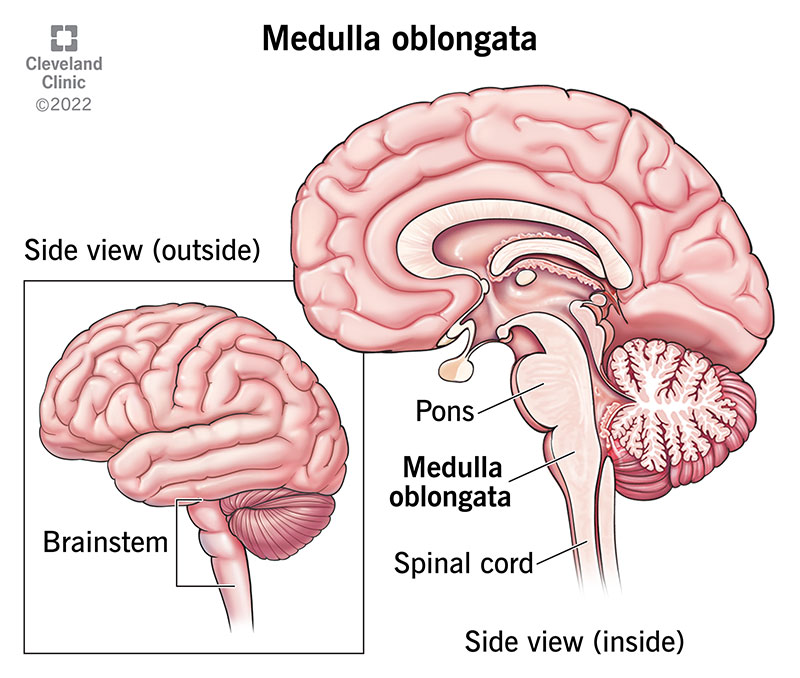

Medulla Oblongata: What It Is, Function & Anatomy

Know Your Brain: Medulla Oblongata

Medulla oblongata | Description, Anatomy, & Function | Britannica

The Anatomy of the Medulla Oblongata

The Medulla Oblongata - Internal Structure - Vasculature

Medulla Oblongata Location, Function, and Features